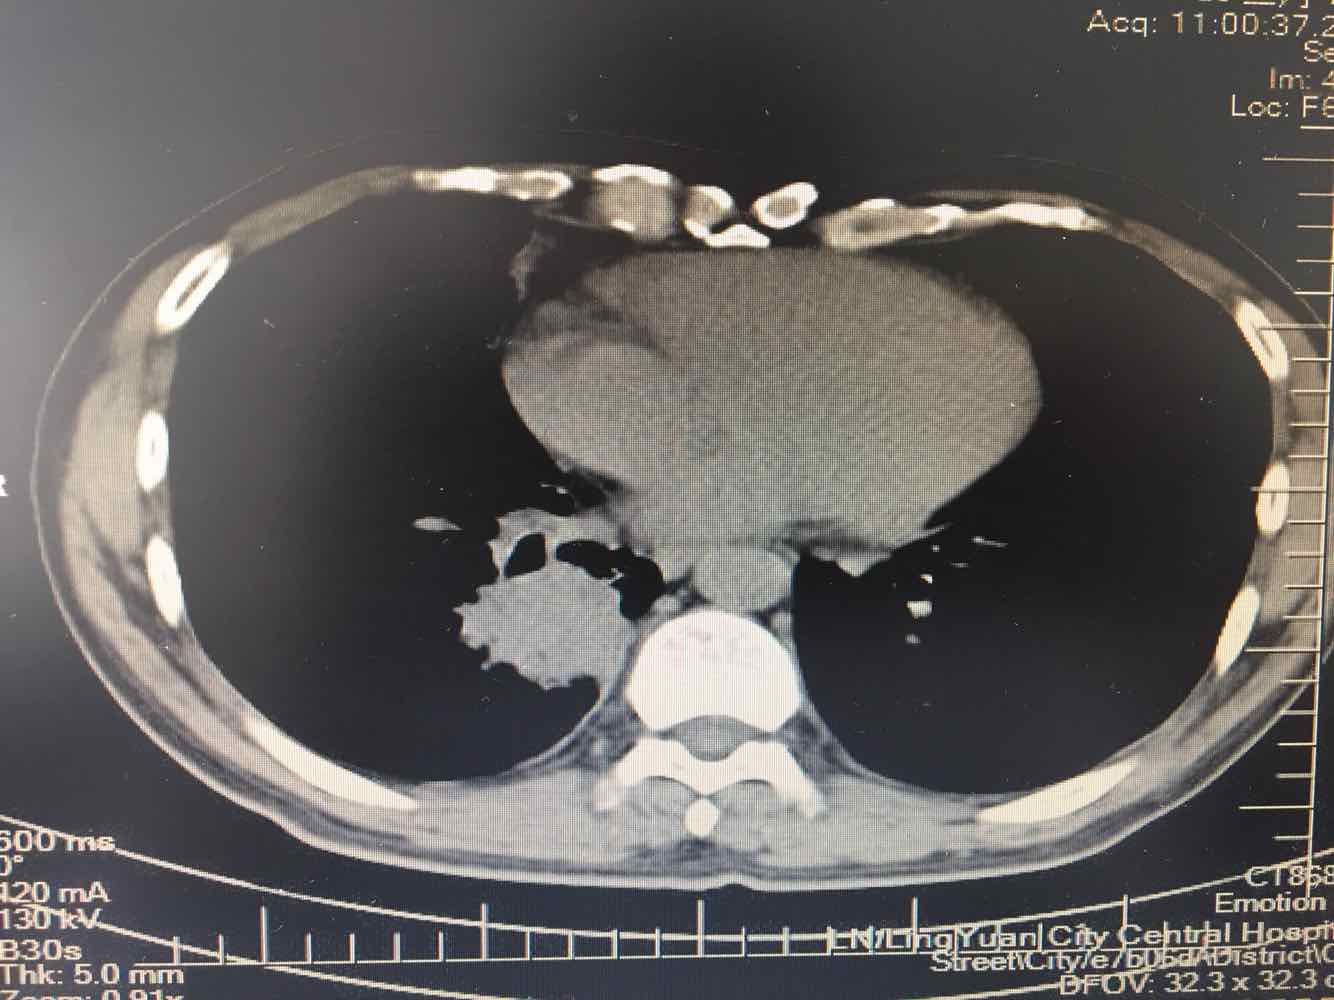

男,45岁,咳嗽,咳痰1个月,发热,盗汗,体重下降5公斤,肺结核病史30年.右肺下叶病变性质待查?